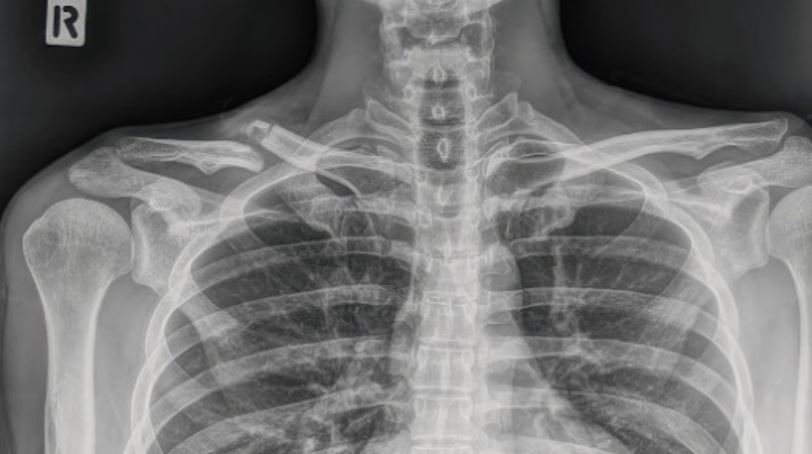

Fractura de clavícula: Muy común, sobre todo en ciclistas de montaña o en aquellos que practican descenso o carretera a alta velocidad. Esta fractura suele producirse por impacto directo sobre el hombro o por transmisión de fuerza a través del brazo al apoyar la mano en el suelo durante la caída. El tratamiento médico más habitual suele ser conservador, con inmovilización mediante cabestrillo y control médico, aunque en fracturas desplazadas o inestables puede ser necesaria la cirugía. Una de las secuelas más comunes es la rigidez del hombro por el tiempo de inmobilización, que puede limitar la movilidad y afectar al rendimiento deportivo. Por eso, es fundamental realizar una rehabilitación adecuada y progresiva, enfocada en recuperar la movilidad, la fuerza y la funcionalidad del hombro para volver con seguridad a la práctica del ciclismo.